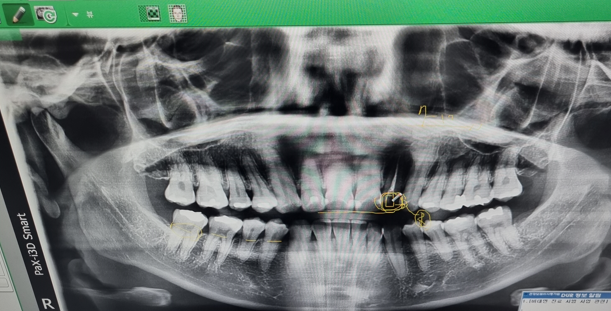

저의 경험상 항암치료를 하면 피부, 항문, 관절통 뿐만 아니라 치아에도 엄청 영향을 주는 것 같아요. 독한 항암제 성분이 우리 입 속 침에도 남아있어서 그런 것 같습니다. 하지만 항암치료를 하면 감염이나 지혈 등에 문제가 발생할 수 있기 때문에 치과치료는 간단한 스케일링도 하지 말라는 안내를 받습니다. 그래서 보통 항암 시작 전에 시간적인 여유가 있다면 치과진료를 미리 받으라고 안내를 받는데, 저는 암수술과 항암치료 시작이 너무 촉박하게 진행되어서 아무런 준비를 못하고 항암을 시작하게 되었습니다. 저는 아이스항암을 6차 진행했는데, 4차까지는 구내염과 잇몸통증으로 고생을 했었고 5차부터 치아 시림 등 통증이 발생해서 막판에 고생을 많이 한 케이스입니다. 그때까지는 주치의 선생님이 치과치료를 하면 안 된다고 하셨었고, 이가 많이 아픈 것은 아니라서 계속 참아왔고 10월에 항암치료 종료 및 1월 추적검사 1차때 피검사 결과 등을 바탕으로 주치의선생님께 치과치료 허락을 받았습니다.

1차 방문 (진단 및 치료계획 설명)

- 사진을 찍어 정확한 치아 상태 파악합니다.

- 사진을 보면서 진료를 진행할 의사에게 설명을 듣습니다.